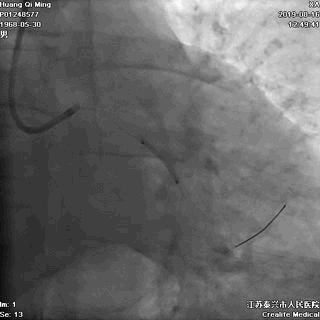

LAD PCI过程

手术器械:

7F EBU3.5

0.014“ Runthrough NS

2.0*20 Maverick

2.5*10 切割球囊

2.5*12 Quantum Maverick球囊

2.0*25 药物洗脱球囊

2.5*25 药物洗脱球囊

导丝通过病变抵达血管远段

8atm,2.0*20球囊行PTCA

8atm,2.0*10 切割球囊对斑块进行切割

16atm,NC球囊对斑块进行预处理

2.0*25 药物洗脱球囊,8atm*60秒释放药物

2.5*25 药物洗脱球囊,8atm*60秒释放药物

术后即刻效果满意